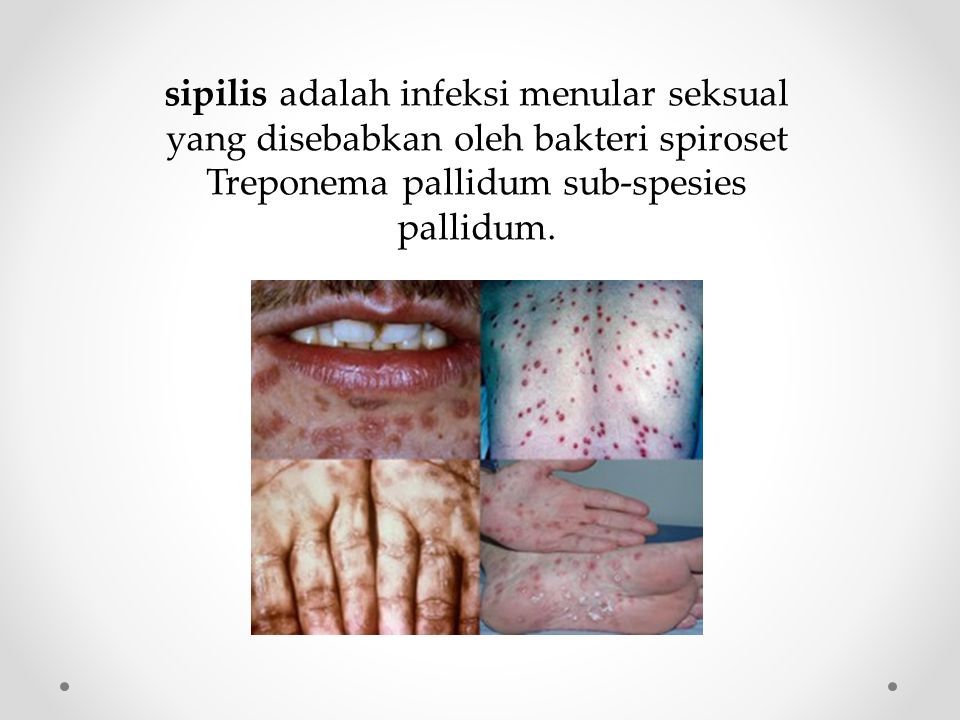

Bakteri Sipilis | Microbiología, Enfermedades de transmision, Enfermedades

Bakteri Sipilis | Microbiología, Enfermedades de transmision, Enfermedades

Inilah Gejala-Gejala Sipilis Pada Wanita | by Oval Dwiputra | Medium

Inilah Gejala-Gejala Sipilis Pada Wanita | by Oval Dwiputra | Medium

Penyakit Menular Seksual Sifilis, Kenali Tahapan dan Gejala Infeksinya Halaman all - Kompas.com

Penyakit Menular Seksual Sifilis, Kenali Tahapan dan Gejala Infeksinya Halaman all - Kompas.com